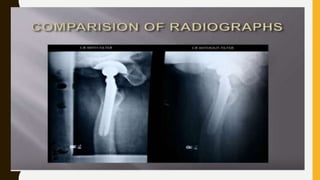

FILTERS & FILTRATION

• FILTERS ARE THE DEVICES USED TO

ATTENUATE OR RESTRICTING THE BEAM

OF XRAY

• FILTRATION IS BASICALLY THE PROCESS

OF ATTENUATING OR SHAPING THE X -RAY

BEAM TO INCREASE THE AMOUNT OF

USEFUL PHOTONS AND DECREASE THE

LOW ENERGY PHOTONS SO THAT WE CAN

GET AN IMAGE WITH BETTER CONTRAST

FILTERS & FILTRATION •FILTERS ARE THE DEVICES USED TO ATTENUATE OR RESTRICTING THE BEAM OF XRAY • FILTRATION IS BASICALLY THE PROCESS OF ATTENUATING OR SHAPING THE X -RAY BEAM TO INCREASE THE AMOUNT OF USEFUL PHOTONS AND DECREASE THE LOW ENERGY PHOTONS SO THAT WE CAN GET AN IMAGE WITH BETTER CONTRAST • (FOR EXAMPLE – A STRAINER IS USED FOR THE SEPARATION OF TEA PARTICLES AND THE TEA ) • THIS ALSO DECREASE THE PATIENT RADIATION DOSE AND OCCUPATIONAL HAZARDS • QUALITY OF X-RAY SPECTRUM SHIFTS TO THE HIGHER ENERGY